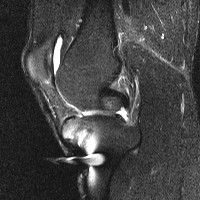

무릎 mri 간단히 봐주실 수 있으시나요 ㅠㅠ

안녕하세요 8년전 십자인대 수술하고 최근 무리한 운동에 무릎 불편감이 생겨서

mri 찍었습니다.

진단결과는 첫 찍은 병원에서 활액막염 이라는 진단을 받았습니다. 혹시 봐주실 수 있으실까요?

올라온 MRI가 단편적이라서 정확한 진단에 어려움이 있지만 십자인대에는 큰 이상이 있지는 않은것 같으며, 무릎관절내 물이 있는 것으로 보아 활액막염의 진단이 맞을 것 같습니다.

하지만 단편적인 영상이기 때문에 촬영병원에서 정확한 판독지 등을 받으시는 것이 좋겠습니다.